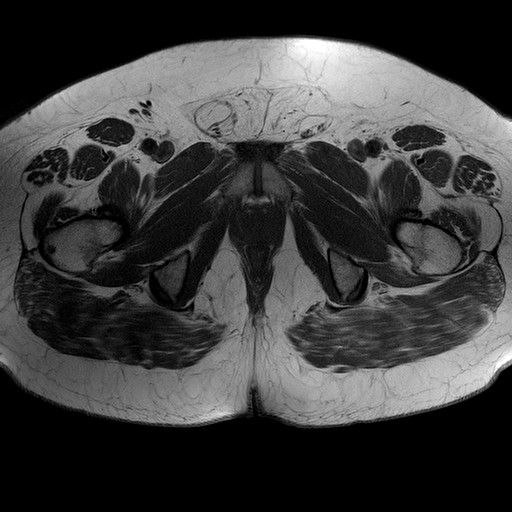

Esami: RMN BACINO

T1W_TSE

Evidenti e simmetriche alterazioni osteofitosiche in regione coxo femorale con riduzione delle rime articolari. Degenerazione completa del cercine glenoideo. Non attuali segni di versamento articolare. Non segni di edema osseo che escludono attuale algodistrofia od osteonecrosi. Lieve e simmetrica riduzione del trofismo della muscolatura glutea.